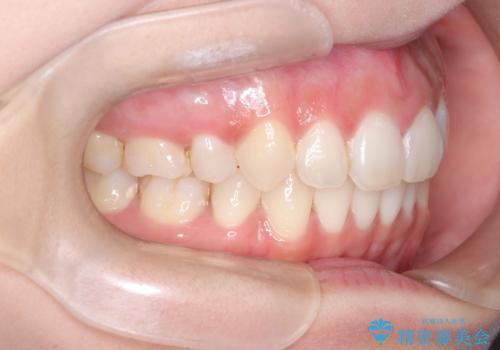

【インビザライン】シザーズバイト、抜歯矯正

- オープンバイトを主訴に来院された患者様です。

抜歯を行うことで、インビザラインを用いて前歯を下げることができ、同時にオープンバイトを改善することができました。

今回はインビザラインのみで治療を終了することができました。